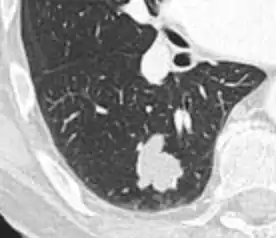

A "notch sign".[9]

- Margin morphology: a spiculated margin is a risk factor for cancer.[8] Benign causes tend to have a well defined border, whereas lobulated lesions or those with an irregular margin extending into the neighbouring tissue tend to be malignant.[10] In particular, spiculations are highly predictive of malignancy with a positive predictive value up to 90%.[9] Also, a "notch sign", which is an abrupt indentation of the nodule, increases the risk of cancer, but may also be found in granulomatous diseases.[9]